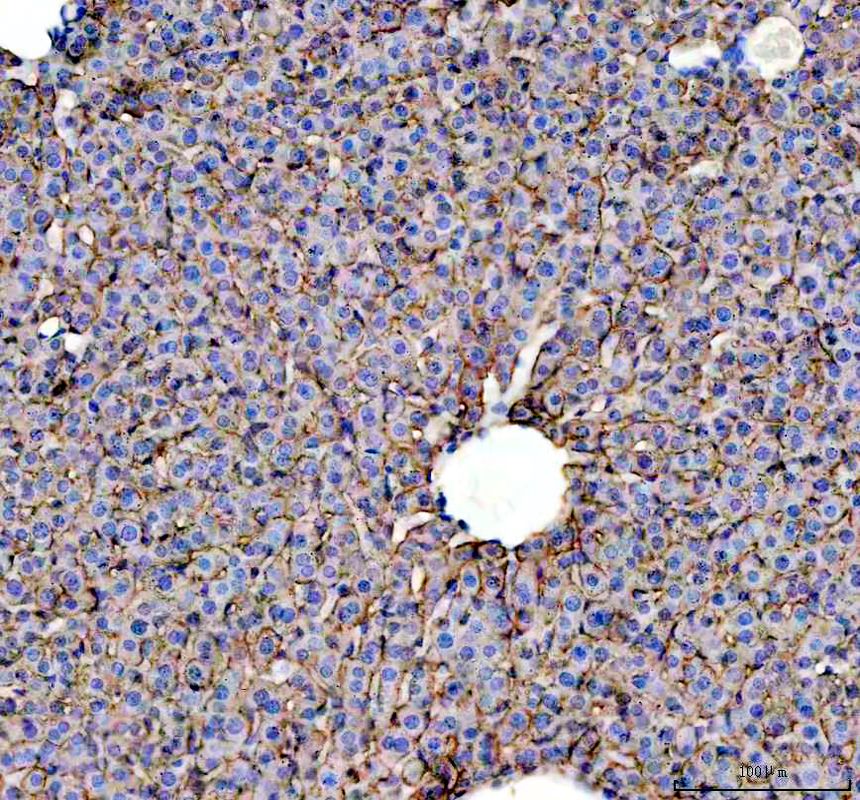

IHC analysis of ASGR1 using anti-ASGR1 antibody (A05376-1).

ASGR1 was detected in a paraffin-embedded section of mouse liver tissue. The tissue section was incubated with rabbit anti-ASGR1 Antibody (A05376-1) at a dilution of 1:200 and developed using HRP Conjugated Rabbit IgG Super Vision Assay Kit (Catalog # SV0002) with DAB (Catalog # AR1027) as the chromogen.